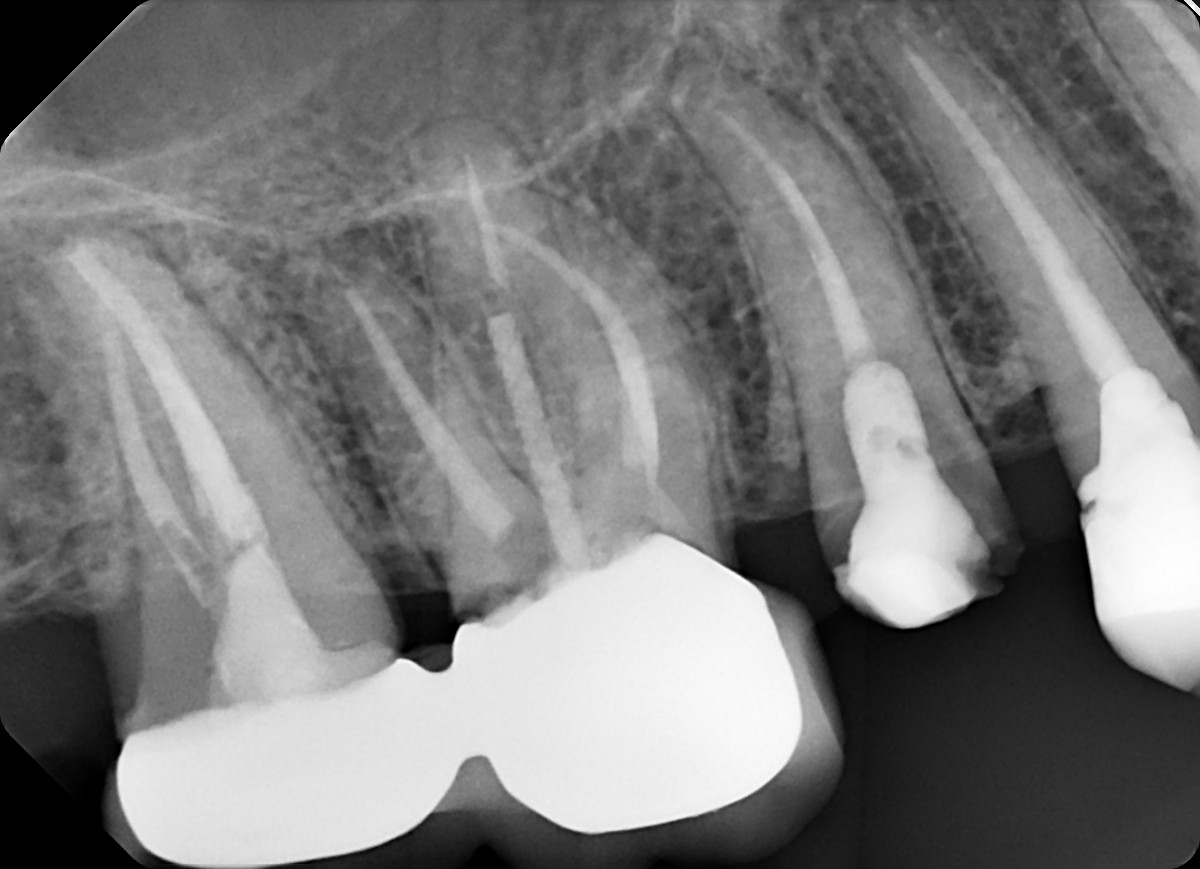

1.  What option can describe the post placement in the X ray bellow for the tooth # 2.5?